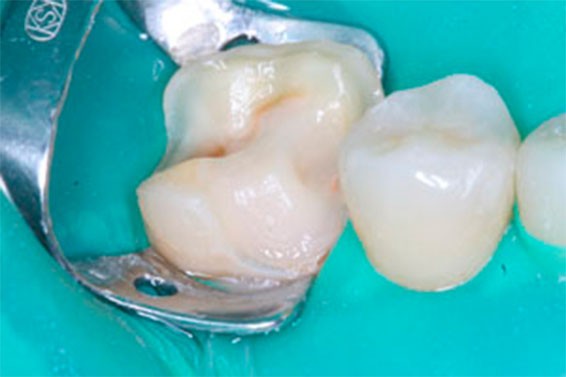

В рамках подготовки к ортодонтическому лечению, на основании результатов диагностики, было принято решение восстановить один из разрушенных зубов керамической реставрацией. Фото 1,2. Обработанный зуб непосредственно перед фиксацией. На фото видно – значительный массив здоровых зубных тканей, которые удалось сохранить, отдав предпочтение именно этому виду реставрации, по сравнению с полной коронкой.

Фото 3,4. Прочность будущей конструкции и ее интеграция в ткани зуба достигается за счет тщательной адгезивной обработки и применению специальных цементов для фиксации. Фото 5. Окончательный вид реставрации в полости рта.